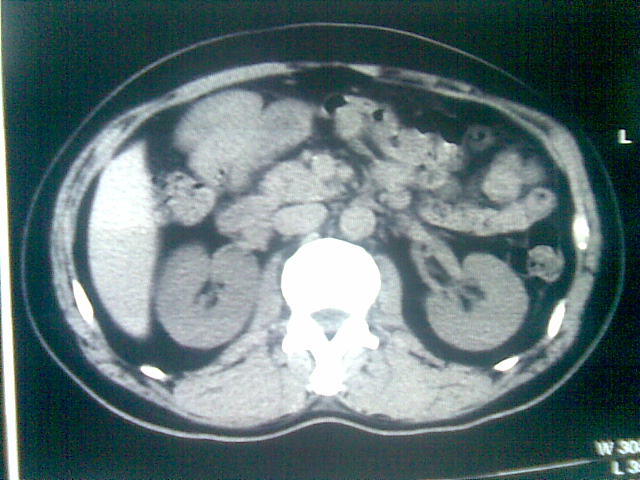

标题: CT23981:男,38岁阑尾炎术后透视胸腔积夜!做CT如下!积液包 [打印本页]

标题: CT23981:男,38岁阑尾炎术后透视胸腔积夜!做CT如下!积液包

可能与阑尾术后关系不太大,1.胸膜增厚粘连见少量气体。包裹脓气胸?左侧网膜囊脓肿?

.胸膜增厚粘连见少量气体。包裹脓气胸

少量积液部分粘连

左侧胸膜增厚、粘连+包裹液气胸。